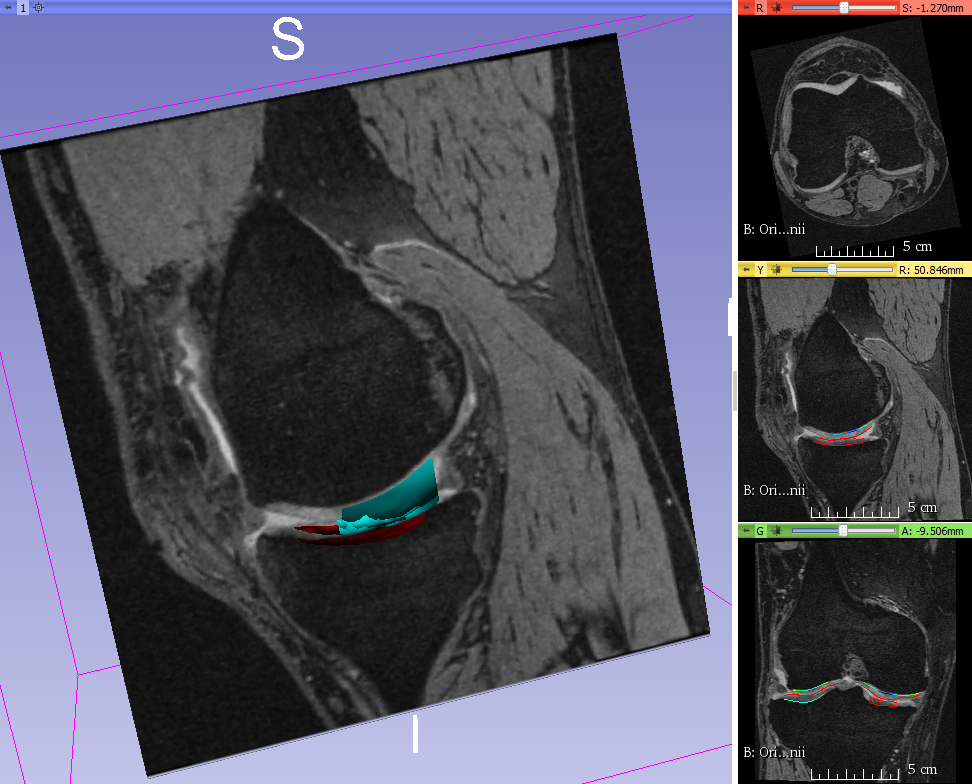

Fig. 8 qualitatively shows the improvement of 4D LOGISMOS over 3D. Note the lack of an obvious edge distinguishing the tibia and femur cartilage. Using the spatial and temporal contextual information from all the time-points, the 4D method is able to correctly position the cartilage for the tibia and femur despite the lack of image information locally.

For analysis of the cartilage structures, accurate segmentation is a crucial first step. In clinical research there is a need for reproducible fully or highly automated segmentation as it offers consistent accuracy and speed over manual segmentation efforts. However, automated knee segmentation is challenging due to the thinning cartilage, appearance of osteophytes, bone marrow and cartilage lesions and surface fibrillation in MRI data. Several of these disease artifacts appear similar to the cartilage further increasing the segmentation complexity (Fig. 8a).

RF classifiers [34] were used to provide better and location-specific cost functions. RF classifiers use the concept of bagging, where for each decision tree a random subset of features is chosen thereby reducing inter-decision-tree correlation, which improves accuracy. A single RF classifier was used in [30] where the limitation was that all the information used was localized along the graph columns. Because of this locality, features were unable to capture information of the neighborhood that appeared larger than a few nodes along the column. There are several anatomical features that appear locally like a cartilage boundary but when examined in a global neighborhood may be combined with pathology (e.g., synovial fluid, Fig. 8). Further, the single RF classifier did not account for the regionally-specific appearance of the surrounding menisci, muscle, bone and other anatomies. As a result, certain intensity profiles appearing in a specific normal-cartilage region of the knee also occurred in another local region in a pathological case. This discrepancy resulted in the improper training of the classifier and contributed to segmentation inaccuracy.